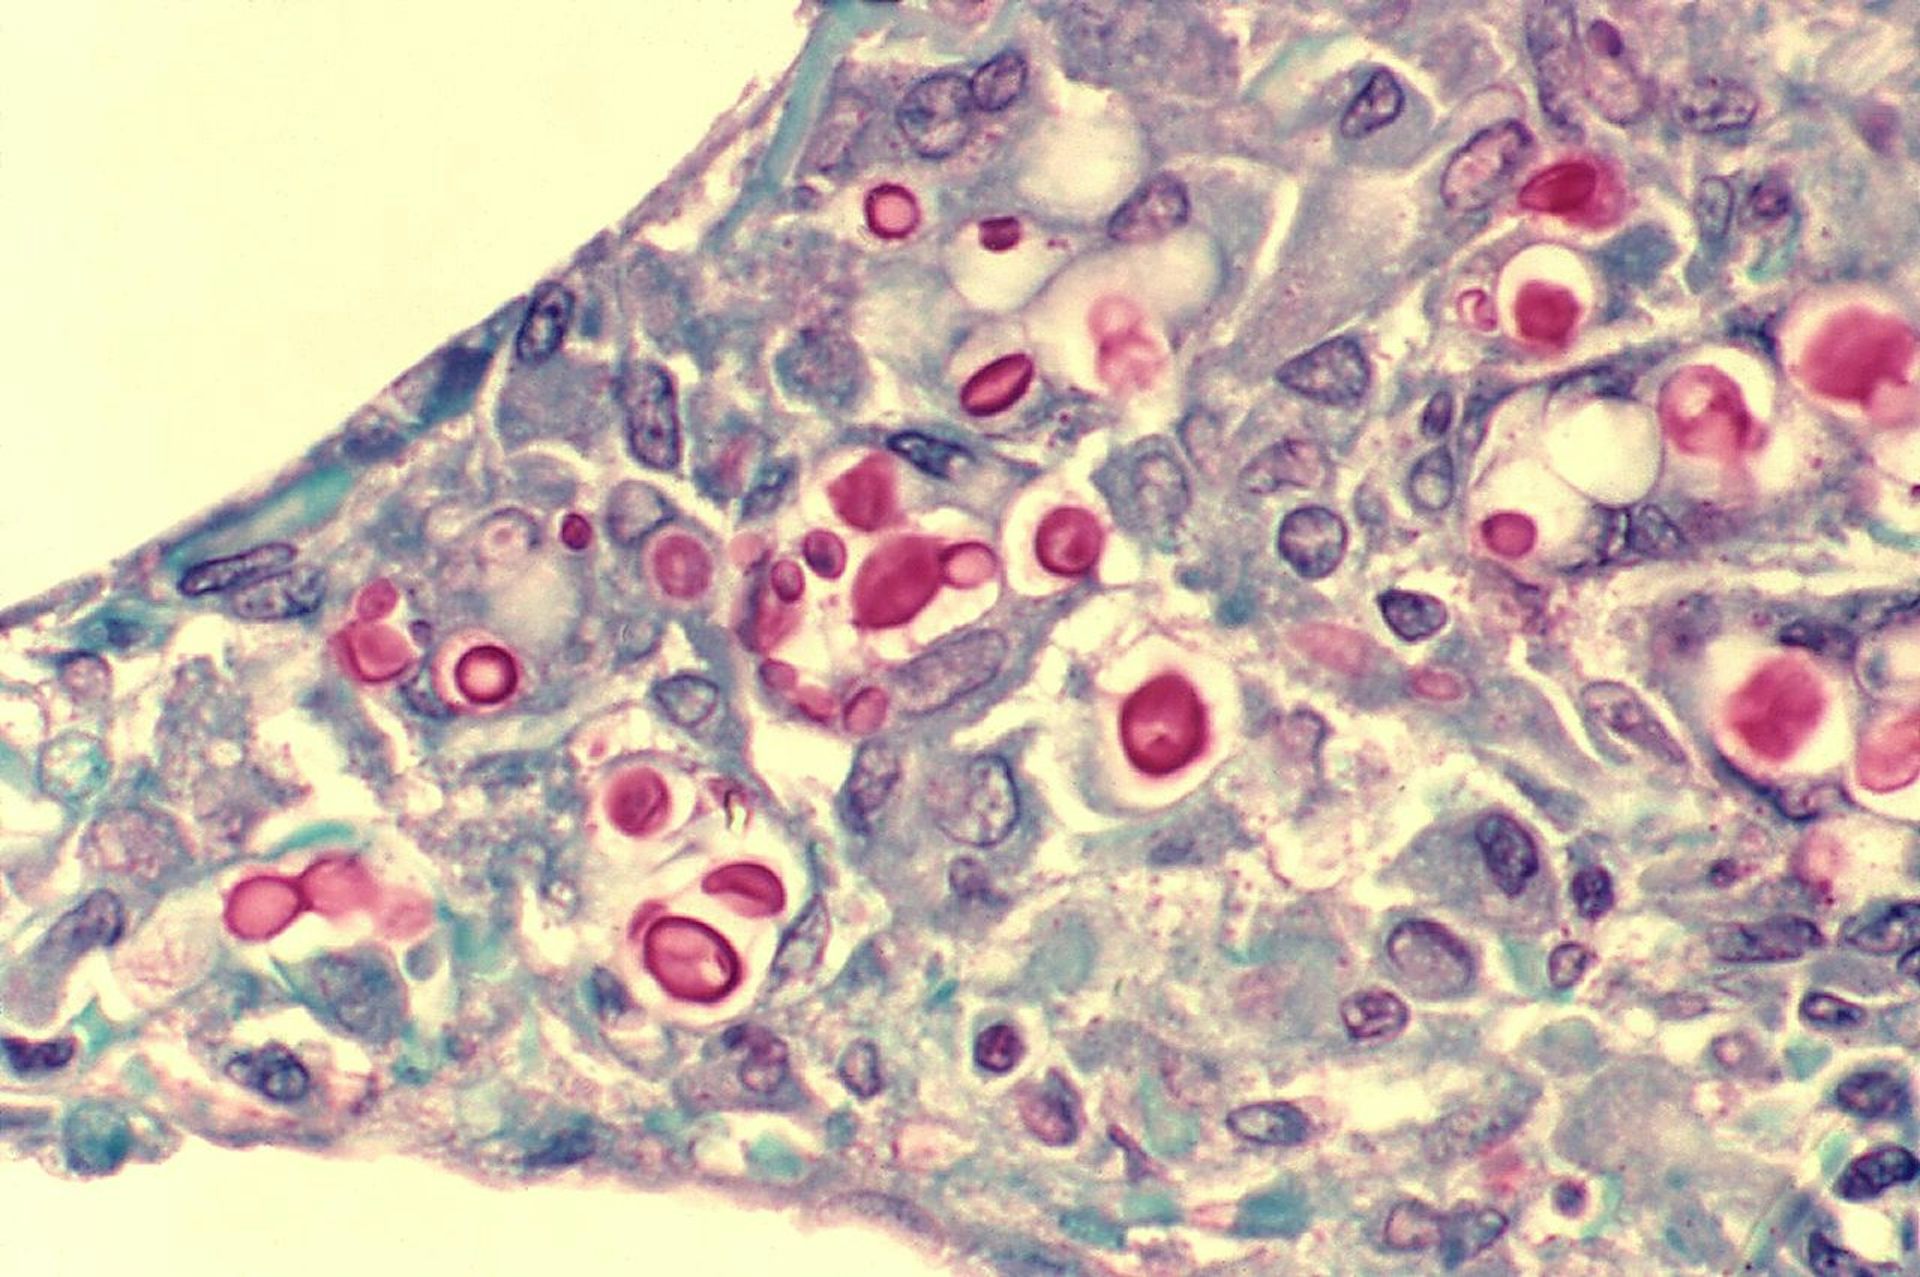

Sebuah laporan Badan Kesehatan Dunia (WHO) terbaru[16] telah mengungkapkan bahwa infeksi jamur menyebabkan lebih dari 1,5 juta kematian setiap tahunnya. Dokumen tersebut mengidentifikasi sembilan belas jamur dan ragi patogen[17] sebagai ancaman terbesar bagi kesehatan manusia. Di antara empat yang dianggap terancam punah[18] adalah ragi Candida auris, sebuah patogen baru[19] yang mampu menyebabkan infeksi serius dan mengancam jiwa.

Nama belakangnya, auris, berasal dari bahasa Latin yang berarti “telinga”, karena pertama kali terdeteksi[20] di saluran telinga pasien. Saat ini, virus ini telah menjadi patogen di rumah sakit[21] yang kebal terhadap banyak obat (menyebabkan infeksi di rumah sakit) di seluruh dunia. Hal ini dianggap sebagai ancaman utama dalam lingkungan perawatan kesehatan[22].